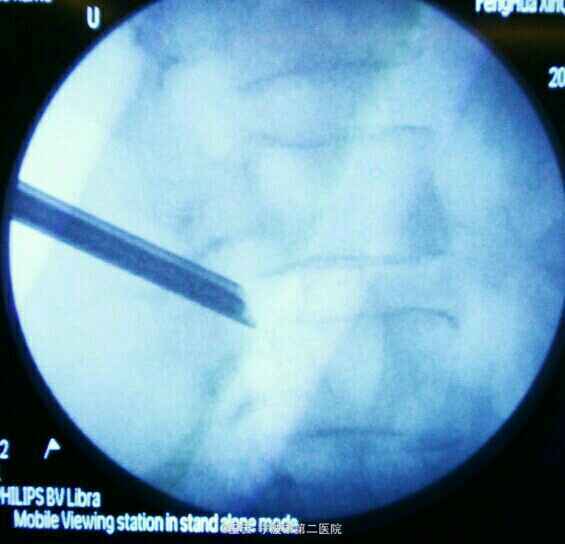

诊断:L3/4椎间盘脱出 治疗:经椎间孔入路椎间孔镜下髓核摘除,射频消融

术后症状立刻缓解,直腿抬高实验80度阴性。